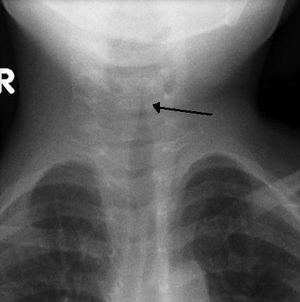

크룹(후두기관지염)은 성대의 바이러스 감염으로, 일반적으로 5~6일 지속된다. 주요 증상은 짖는 듯한 기침과 저열이다. X선 사진에서 크룹은 기관의 협착을 나타내는 "첨탑 징후"로 확인할 수 있다.